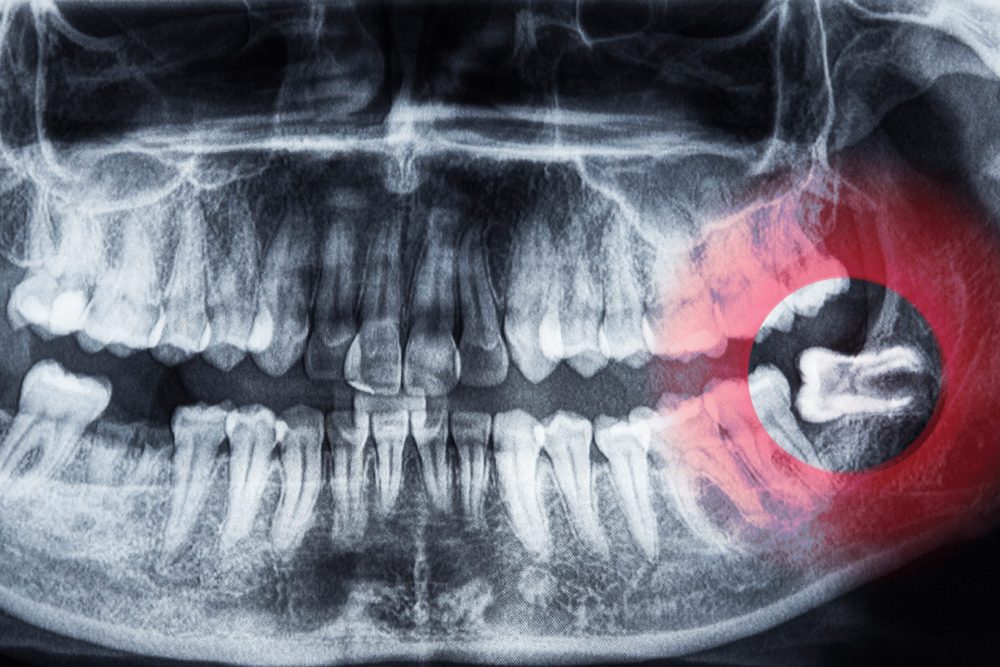

1.斜めや横向きに生えている

歯ぐきから顔を出しながら、斜めや横向きに生えている親知らずは、抜いた方がいいケースが多いです。

斜めに生えた親知らずは、隣の奥歯を圧迫し続けます。

長期間押されると、隣の歯の根っこが少しずつ溶けてしまう場合があります。

また、親知らずと隣の歯の間にできたすき間には、食べかすが溜まりやすく、歯ブラシの毛先も届きにくいため、汚れが残りがちです。

このままだと、親知らずだけではなく、隣の健康な歯まで虫歯になるケースも少なくありません。